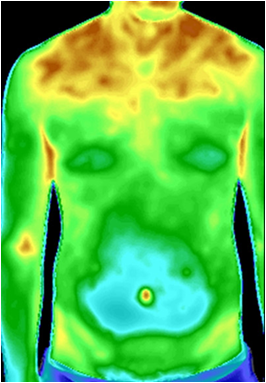

图1 肠道功能失调红外热成像图